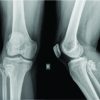

The magnetic resonance imaging (MRI) revealed an expansile lesion with no associated soft-tissue component. Pre-operative angiography was done to confirm perfusion of the deep branch of the medial femoral circumflex artery and to detect eventual alteration of its normal course cranial to the lesser trochanter and dorsal to the greater trochanter. The provisional diagnosis of sessile solitary osteochondroma with probable sarcomatous degeneration and secondary hip osteoarthritis (OA) was considered after radiographic evaluation. The patient was explained about the possibility of sarcomatous degeneration of the tumor, considering its longer duration of symptoms and the presence of rest pain. Under general anesthesia, the patient was placed in a left lateral position. Through the posterior approach, the proximal femur was exposed, retaining the short external rotators with a sleeve of cortical bone. The tumor was found to be involving the medial and posterior cortex of the proximal femur. The femoral head was dislocated posteriorly after performing a capsulotomy. Wide excision of the tumor by excision of the entire proximal femur was performed to remove the osseous base to avoid any chances of recurrence (Fig. 2). Diaphysis was reamed according to pre-operative templating. Serial reaming of the acetabulum was done, followed by the implantation of a cemented acetabular cup. A distally inter-locked modular Hydroxy apatite-coated femoral reconstruction prosthesis (REEFTM, Depuy) was used on the femoral side (Fig. 3). Intraoperative samples were sent for histopathological examination.

Histopathological examination: Sections showed a cartilaginous cap with underlying bone and areas of enchondral ossification. The cartilaginous cap was microscopically measured to be 2.2 mm mature hyaline cartilage overlying fibrous perichondrium. Bony trabeculae enclosing marrow noted trilineage hematopoiesis. No evidence of necrosis, pleomorphism, or sarcomatic changes was observed. The patient was mobilized with partial weight bearing for the initial 6 weeks, followed by full weight bearing mobilization. The patient has been under follow-up for the past 10 years, during which time she has exhibited good clinical outcomes. On follow-up radiographs, there were no signs of recurrence. The hip ROM was assessed with a Modified Harrison Hip Score (MMHS) and Visual Analog Score (VAS). MMHS improved from 35 at the 1st month follow-up to 60 at 1-year follow-up. At the 2-year follow-up, MMHS was 80. VAS improved from 4 at the first follow-up at 1 month to 0 at the on-year follow-up. The patient score was maintained for the subsequent follow-ups.